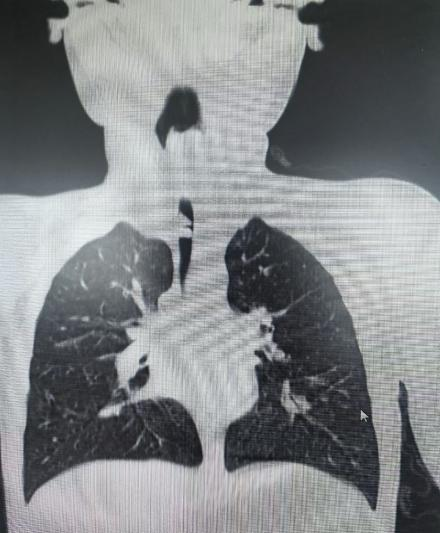

据悉,患儿小顺(化名)随父母从上海返皖探亲,夜间突发气促、喘息,外院初诊为“支气管炎、哮喘”,但治疗一天后症状反而加剧。转入安徽省儿童医院后,急诊胸部CT及气道三维重建提示疑似气道异物,病情危急。儿童呼吸科主任医师王玉带领团队迅速为患儿进行急诊支气管镜检查,发现其气管中段有一巨大肿物,堵塞管腔约4/5,仅存一丝缝隙维持通气。

为尽快解除呼吸危机,医院立即启动多学科协作机制。经全面评估,团队果断施行支气管镜下肿瘤切除术。手术中,医生运用电圈套器完整套取肿瘤组织,再以激光精准清除基底残留病灶,在彻底切除肿瘤的同时,最大限度保护了正常气道黏膜。手术全程仅用时40分钟,出血量不足5毫升,实现了微创、精准、安全的治疗目标。术后病理确诊为“炎性肌纤维母细胞性肿瘤”,属于临床罕见的气道肿瘤类型。